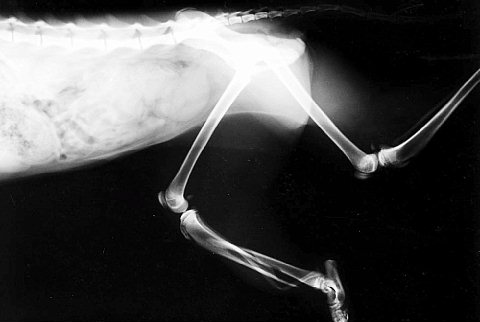

これは別件でレントゲンを撮ったらこんなんでした、という症例です。話によると1年ぐらい前に交通事故にあったようで足がプランプランだったらしいんですが放置していたらそのうち歩けるようになった、とのことでした。骨は変な形でくっついていました。これで普通に歩けてたんです。これは猫なんですが、不思議と言うか力強い動物です。